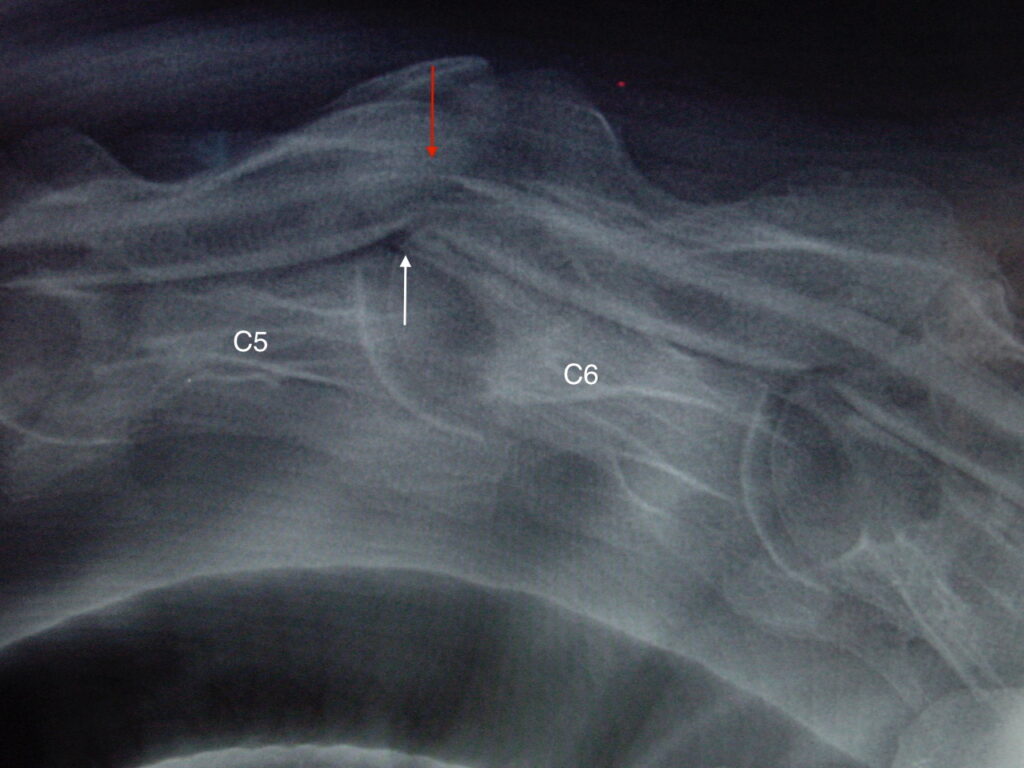

Obrázek 5: Rentgenový snímek krku s jasnou dynamickou kompresí na úrovni C5–C6, kontrastní látka téměř zmizela nad (červená šipka) a pod (bílá šipka) míchou

Proto se ataxie někdy projevuje pouze v okamžiku, kdy je kůň korektně ježděn na přilnutí, a dokonce v tu chvíli může začít i kulhat. Jakmile jezdec povolí otěže, kulhání vymizí. Naopak u koně se statickou kompresí (obr. 4) dochází ke stlačování míchy neustále, bez ohledu na polohu krku. V těchto případech dochází k závažnějšímu poškození míchy a kůň musí být léčen co nejdříve, aby nedošlo k trvalým následkům na míše.